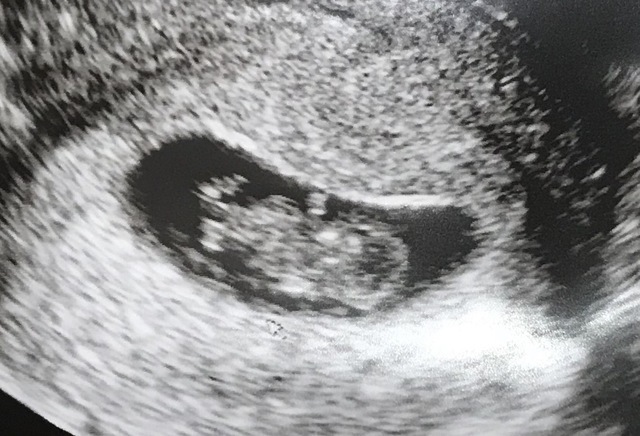

8週1日(8w1d・女の子)|やまやま06 さん(27歳)

エコー写真撮影時のエピソード:

2回目の健診でのエコー。

無事に育っているか不安でしたが形が少し出来てきていて、成長してくれているんだなと実感。悪阻はほとんどなく過ごせていました。

義理の両親にもこの時くらいに報告。 すごく喜んでくれ、私の体調も気にかけてくれるようになりました。